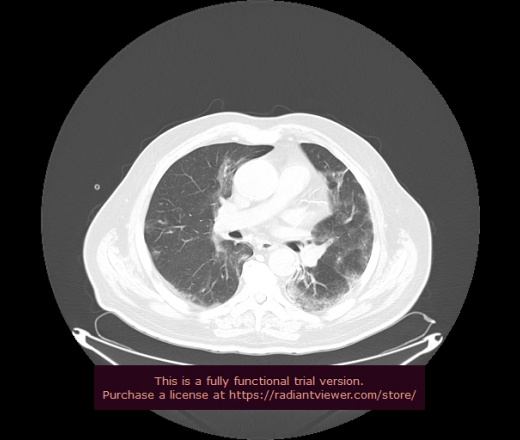

Уважаемые коллеги, если имеется интерес, сможете ли Вы спрогнозировать дальнейшее +-одинаковое течение процесса у 4 данных разных пациентов? Зацепиться где-то можно очень просто, где-то нельзя.